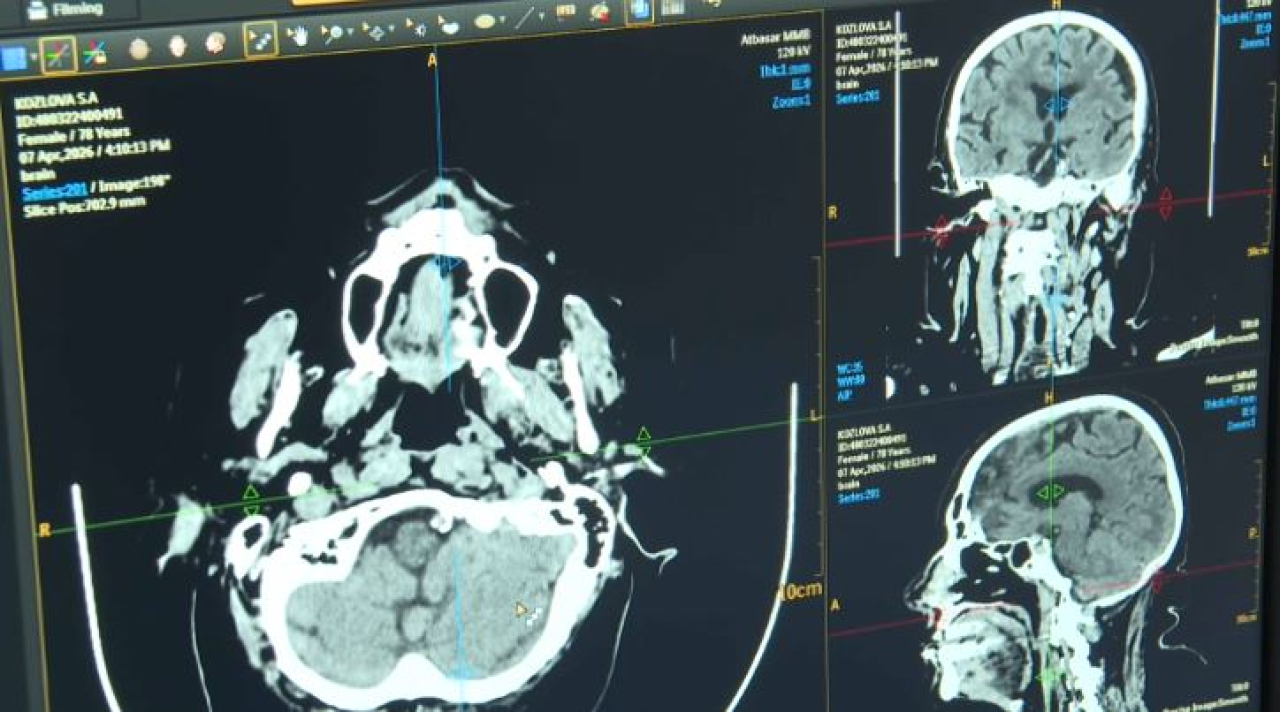

Врачи Акмолинской области используют искусственный интеллект для диагностики инсульта. Программа Cerebra AI анализирует КТ-снимки головного мозга и выявляет симптомы заболевания за считанные минуты. Новую технологию применяют в двух медучреждениях региона. Как искусственный интеллект повлиял на качество диагностики заболевания, узнавала...